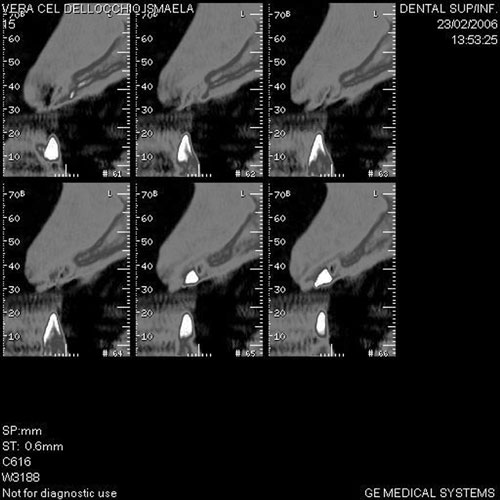

Mientras dichos movimientos ortopédicos se producen (período que supondrá otros seis meses), estudiamos los actos quirúrgicos a realizar en los cuatro implantes que pondremos. De acuerdo al estudio Desatascan realizado observamos tres situaciones diferentes: 1º-El Primer Molar Inferior Izquierdo, lo instalamos mediante Cirugía Minimamente Invasiva , con la aplicación de una Férula Quirúrgica Obtenida de los datos del scanner tratados con un programa de CMI (Cirugía Minimamente Invasiva), previa prueba en un modelo estereolitográfico, ya que la altura ósea era apenas de 9 mm. 2º- El Primer Molar Superior Derecho, se implantará mediante una ligera Elevación Atraumática (Trans alveolar) de Seno una vez logrado el espacio mesio distal necesario. 3º- El Incisivo Central Superior Derecho ausente, cuenta con un sustrato óseo prácticamente inexistente. El espesor de la tabla era de menos de 2 mm. Los caminos posibles a seguir para contar con una Rehabilitación de piezas independientes son dos: Optamos por esta segunda opción por ser menos cruenta y no necesitar de una zona dadora. Técnica esta que pondremos en práctica en dos etapas diferidas: 1º-Incisión horizontal palatinizada, incisiones peri rodetes gingivales e incisiones de descarga. Dilatación que comenzamos con dos incisiones de descarga sobre la cortical vestibular realizadas con disco. y el comienzo de la dilatación propiamente dicha mediante una hoja de bisturí, para luego seguir con un periostótomo . Recién después de alcanzada una cierta separación de la cortical vestibular de la palatina, empezamos con los dilatadores roscados. En este punto podríamos haber utilizado sin riesgos un Implante de 3,8 mm de diámetro, pero a fin de mejorar la estética del pilar emergente decidimos rellenar con material osteoconductor y osteoinductor (BiOss) y cubrir mediante membrana reabsorvible ( Bio Guide). 2º-Implantación seis meses después. Mientras se van cumpliendo los tiempos antes mencionados, y comprobamos reiteradamente la funcionalidad de la oclusión con los provisorios, tomamos impresiones definitivas y construimos primero el maxilar inferior, para definir en primer término la porción inferior de la Guía Anterior., y a nivel posterior Curvas y Microplanos. Para luego realizar los cuadrantes premolar- molar del superior: La espera de la regeneración ósea y sus tiempos pertinentes, más la espera de los tiempos de la implantación, nos obligaron a modificar las etapas del protocolo D.AT.O de manera de mantener la –D- mediante el sector superior de la GA. en provisorios, mientras fuimos resolviendo en forma definitiva los demás sectores. Ya pasados los meses necesarios para recrear un hueso adecuado en el área del Incisivo Superior Derecho, procedemos a resolver la implantación de dicha zona, observando que todo el esfuerzo dedicado al mismo había sido inútil, ya que la formación de hueso se produjo minimamente. Cuatro meses después tomamos impresiones del sector Antero Superior de la Guía Anterior, incluyendo el arrastre de un transfer . Seguimos modelando la encía con un nuevo juego de provisorios. Y se construye entonces el sector superior de la Guía Anterior. Se efectúa un control radiográfico a los 6 meses. Se ha intentado mostrar en esta Rehabilitación, que a pesar de las distintas circunstancias de cada paciente, siempre debemos tener en cuenta la necesidad de ejercer la DESOCLUSIÓN del caso como prioridad número uno, para luego perseguir la ALINEACIÓN TRIDIMENSIONAL de las arcadas y obtener así una OCLUSIÓN equilibrada. D.AT.O. ES EL PROTOCOLO QUE DEBEMOS SEGUIR EN TODA REHABILITACIÓN. BIBLIOGRAFÍA 1)William Mc Horris,B.S.,D.D.S. Oclusión. Con especial énfasis sobre :El rol funcional y parafuncional de los dientes anteriores. 2)Von Spee , Craff(Anatomista alemán, describió la curva de compensación de la articulación de molares y premolares).CURVA DE SPEE 1.89 3)Stuart,D.”Some aspects of the inervation teeth.”Procedings of Royal Society of Medicine.20:1675,19274)Muhleman,H. y Savdir,S”Tooth movility-its causes and significance”Journal of Periodontology ,36:153,Marzo ,Abril,1965. 4)Muhleman,H. Y Savdir,S”Toothmovility its causes and significance” Journal of Periodontology,36:153,marzo,abril,1965. 5-Oclusión y Diagnóstico en Rehabilitación Oral. 6-Anatomia Odontológica. 7-A contribution to the study of the movementes of the mandible. 8-Celenza F.W, Nadeskin J.F.,Oclusión.Situación actual. 9-D´Amico 10-Dawson P.E. 11-Huffman –Regenos. 12-Hobo S.-Takayama H.A. 13-Lucia V.O 14-Mc Horris. 15-Mc Horris. 16-Stuart C. 17-Vartan Veshnilian 18-Alvarez Cantoni H. AUTOR:Ratificación del Protocolo en Rehabilitación Bucal a pesar de las incidencias propias de cada caso clínico. A propósito de un caso.

Tridimencionalización mediante implatemetric y ensayo de colocación de implantes

Tridimencionalización mediante implatemetric y ensayo de colocación de implantes

Perforación de prueba en mod. esteorlit.